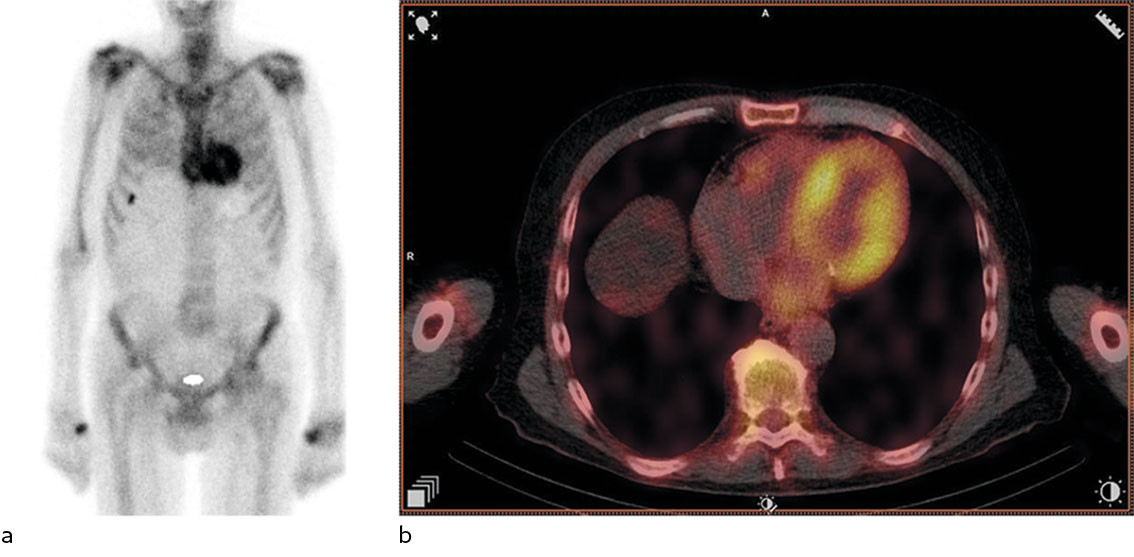

Ekkokardiografi avdekket global biventrikulær hypertrofi med endediastolisk septumtykkelse 17 mm (6–10 mm) (figur 1). Det var redusert langakseforkortning med relativt bevart funksjon apikalt. Myokard hadde et påfallende spettet ekkosignal, mest uttalt i septum. Ejeksjonsfraksjonen var 45 % (≥ 52) og den globale longitudinelle tøyningen −12 % (−18 til −22). Venstre atrium var dilatert. Det ble ikke avdekket klaffefeil av betydning. Pasienten hadde ingen synlig perikardvæske. Koronar angiografi ble utført påfølgende dag og avdekket ingen signifikante stenoser. Funn av økt veggtykkelse, spettet myokard og påfallende redusert langaksebevegelighet med bevart funksjon apikalt vekket mistanke om avleiringssykdom, og videre utredning ble igangsatt.

Grunnet de ekkokardiografiske funnene henviste behandlende lege til skjelettscintigrafi med technetiummerket 3,3-difosfono-1,2-propanodikarboksylsyre (99 mTc-DPD), som ble utført fem dager senere, mens pasienten var inneliggende. Det ble også tatt prøver til urin- og serum-proteinelektroforese. Skjelettscintigrafi avdekket høyt DPD-opptak i hjertet, Perugini-grad 2 (figur 2). Proteinelektroforese avdekket monoklonal komponent (M-komponent) bestående av IgA-kappa. Det var forhøyede frie kappa-kjeder (850 mg/L (4–25)) og frie lambda-kjeder (33 mg/L (6–27)). Kappa/lambda-ratioen var 25,8 (0,5–1,6), klart patologisk.

Skjelettscintigrafi er en nukleærmedisinsk undersøkelse som brukes ved mistanke om patologiske tilstander i skjelettet, for eksempel metastaser. 99 mTc-DPD-scintigrafi har vist seg å ha svært god diagnostisk nøyaktighet for kardial ATTR-amyloidose, forutsett at AL-amyloidose er utelukket gjennom urin- og serum-proteinelektroforese (4). DPD-opptaket i myokard graderes etter Peruginis skala fra 0 til 3, avhengig av hvor stort opptaket i myokard er sammenliknet med skjelettet. Grad 2–3 sees typisk ved ATTR-amyloidose (5). Ved AL-amyloidose ses som oftest intet (grad 0) eller lett økt opptak (grad 1), men grad 2–3 ekskluderer ikke AL-amyloidose (4). Flere bifosfonater, for eksempel hydroksydifosfat og pyrofosfat, kan også brukes for å påvise hjerteamyloidose.